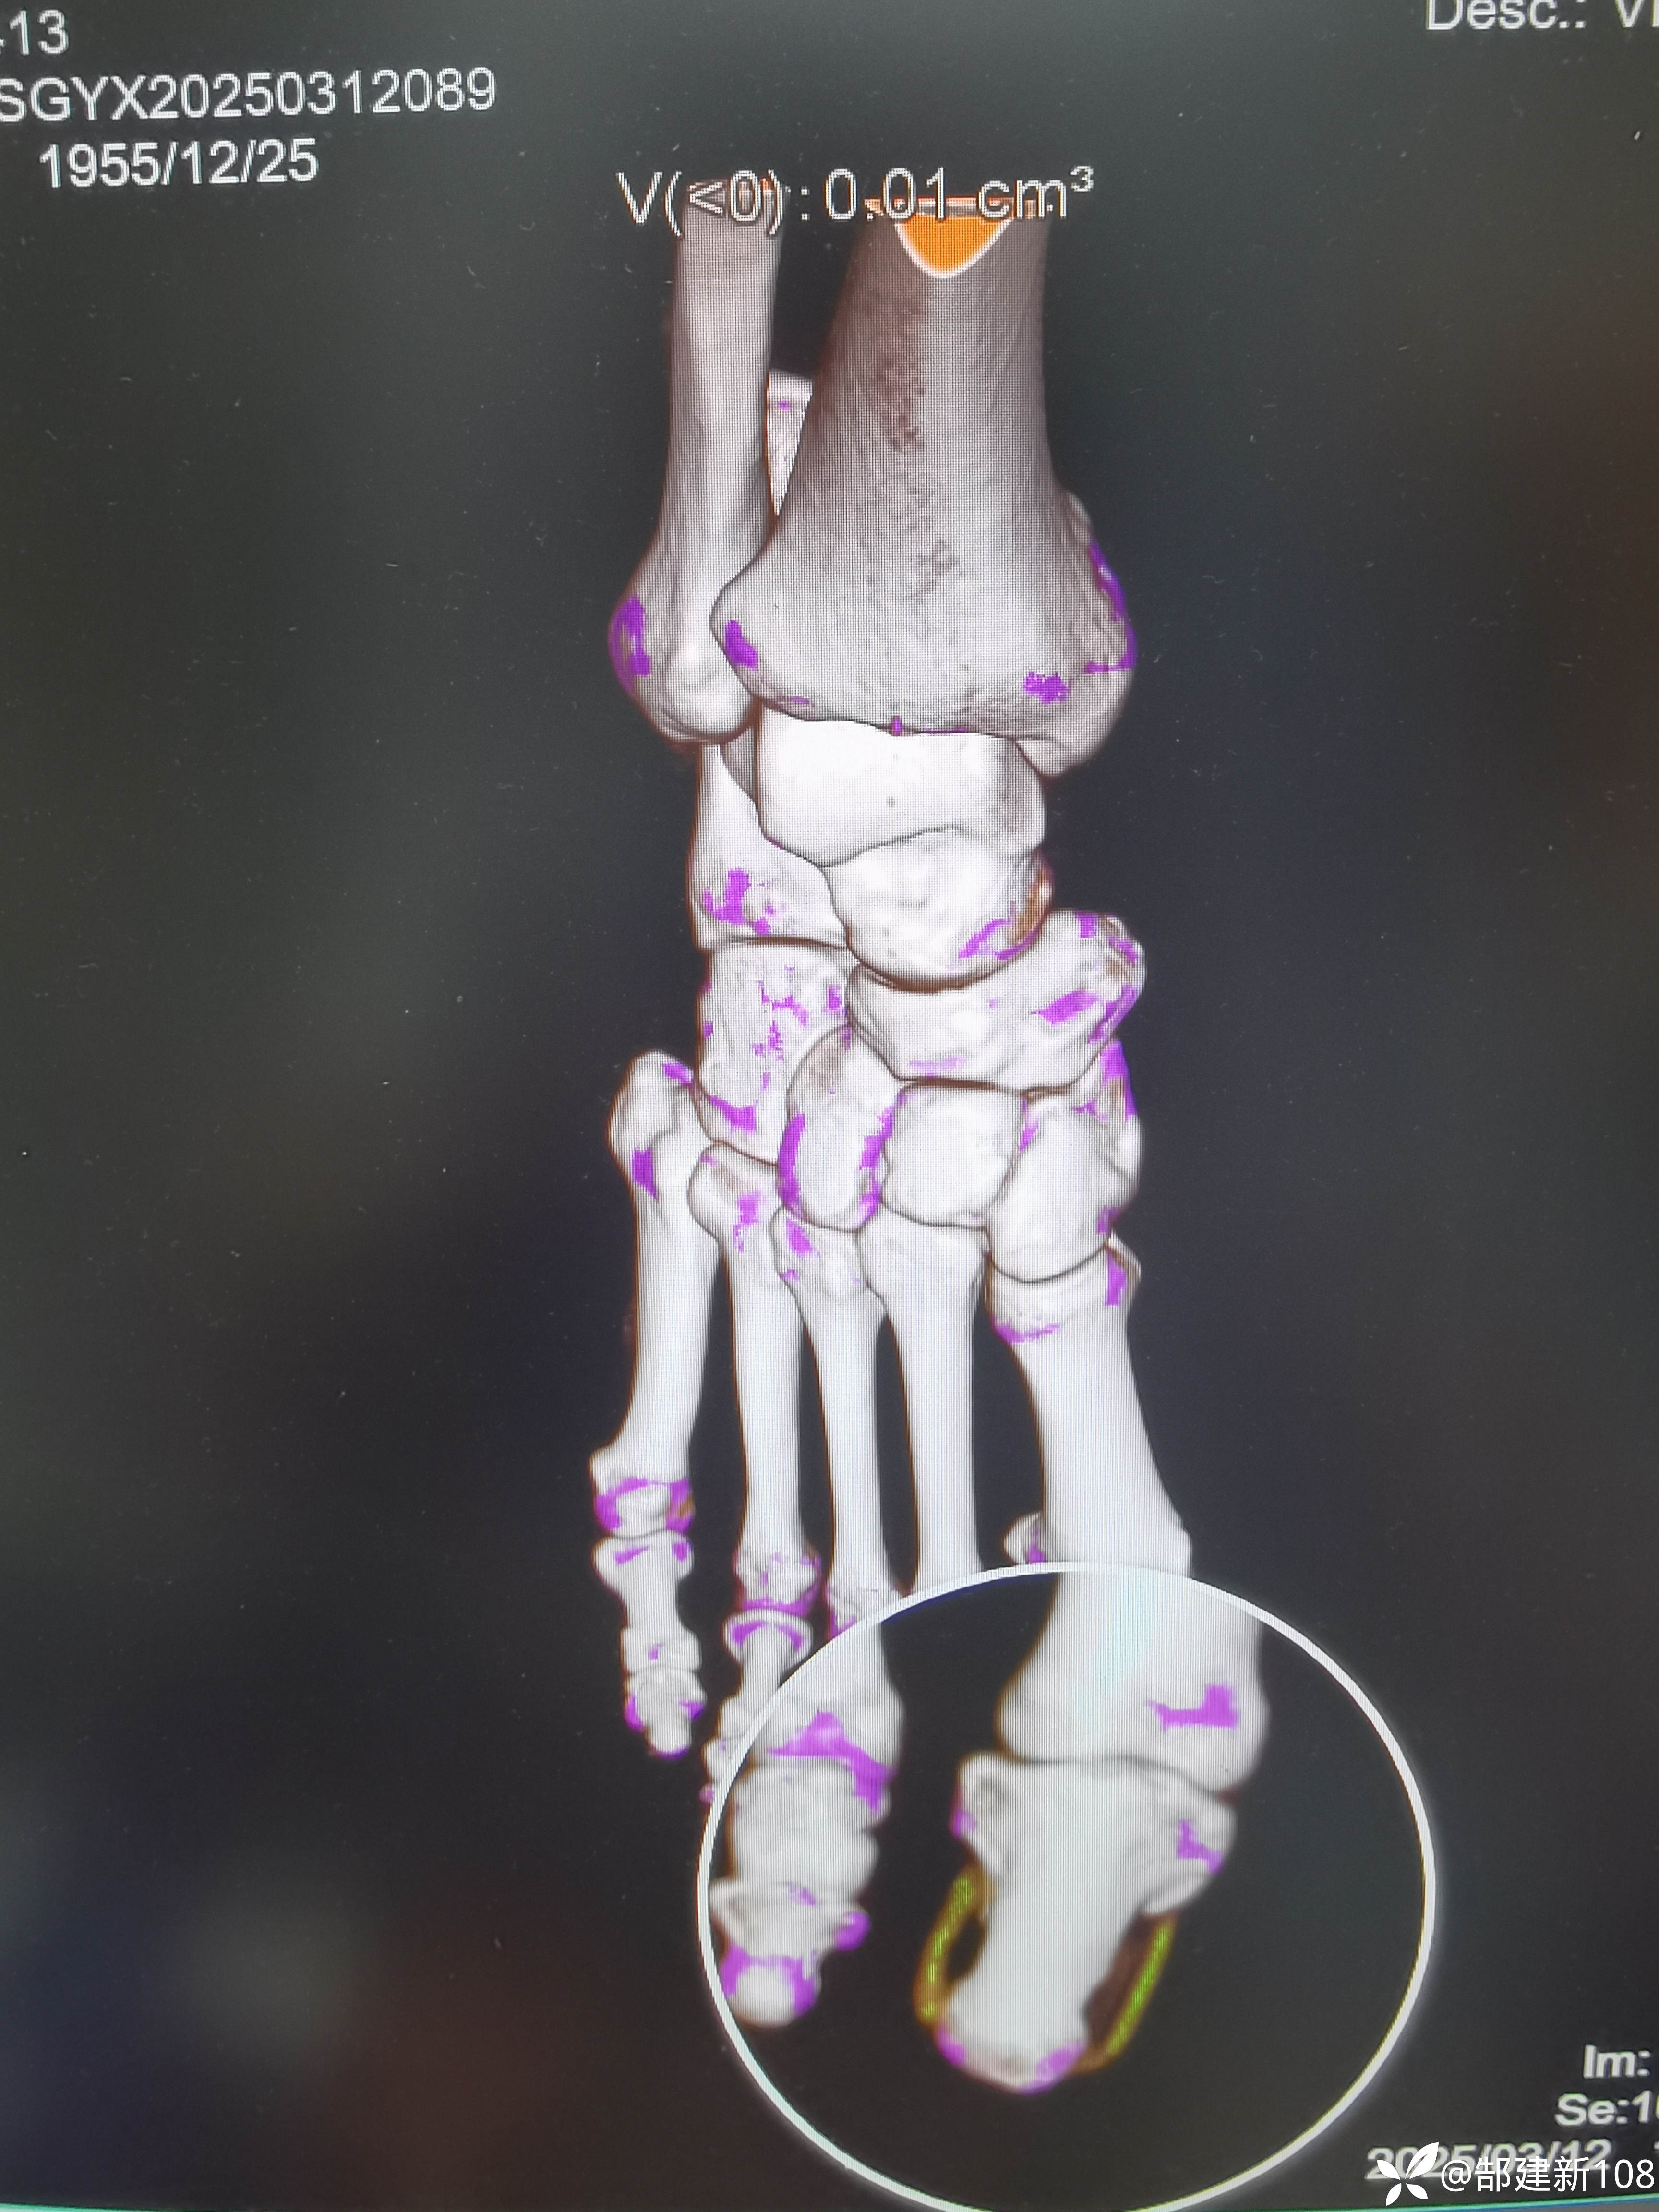

患者男,45岁,尿酸增高3年,足部发作疼痛3天。

筛查早期痛风石可以用双源CT来帮忙,能量成像伪彩色查到绿色的地方可以用读片放大镜或缩放功能可以发现小米粒大小的痛风石。